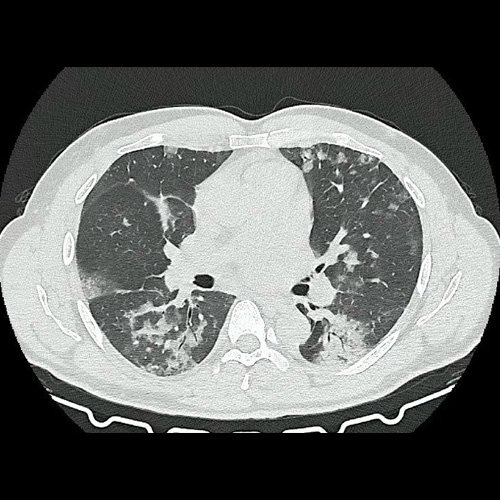

• Tomografía de tórax sin contraste endovenoso (Dia 0):Se observan múltiples áreas de consolidación parenquimatosa con broncograma aéreo y de distribución difusa por ambos pulmones, predominando en los lóbulos inferiores, asociadas a engrosamiento de los septos y rodeadas de tenue vidrio esmerilado. Se identifican estructuras ganglionares lateroaórticas, pretraqueales y subcarinales, ninguna de ellas sin alcanzar rango megálico.

Tomografia de torax sin contraste endovenosos (Ventana pulmonar-corte axial)